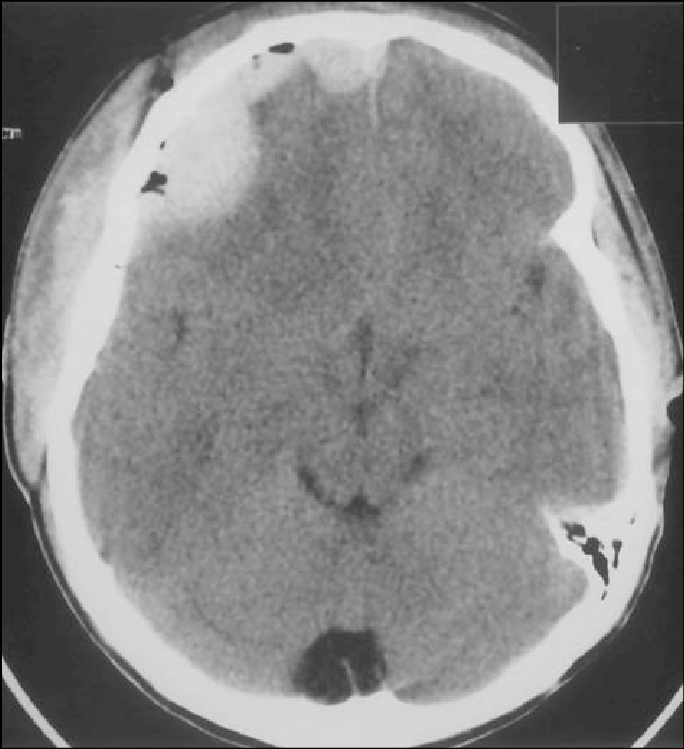

Presence of air in an epidural hematoma

Suggests fracture of the sinuses or mastoid air cells